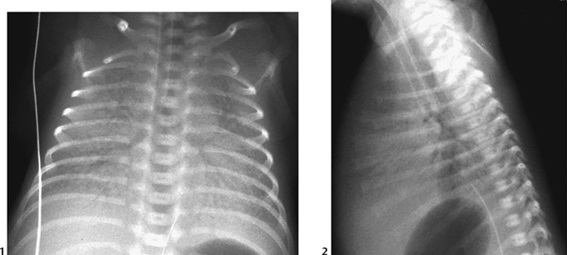

Antero-posterior chest X-ray - low lung volumes, ground-glass reticulo-granular appearance with air bronchograms |

Neonatal pneumothorax secondary to respiratory distress syndrome (Romania)

Clinical Area: Pulmonology

We report the case of a preterm male newborn, the second twin, with very low birth weight and a gestational age of 32 weeks who was born in a 1st level maternity and transferred to our 3rd level maternity at 10 hours after birth. At admission, he presented functional respiratory syndrome represented ...